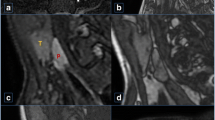

The different phases were reviewed side-by-side, as demonstrated in Fig. 2. In this example, we identified a parathyroid adenoma posterior to the left thyroid lobe in close relation to the common carotid artery. The different phases were also reviewed in absolute relation to their timing. This allowed us to plot the various phases on a curve depicting enhancement over time, as demonstrated in Fig. 3. In the example shown, arterial wash-in and venous wash-out of a suspected parathyroid adenoma were demonstrated with ease. Motion artifacts due to swallowing were present on a single phase in this specific example, affecting the curve of the small parathyroid lesion (34 s after administration of contrast).

Axial images at the level of the thyroid at different time intervals. Scans at 0–20–22–24–26–28–30–32–34–36–38–40 s after administration of contrast, left to right from the top. Suspected parathyroid adenoma posterior from the left thyroid lobe in close relation to the common carotid artery (arrows). Note the lower enhancement on NECT (red arrow), higher enhancement compared with the thyroid in the arterial phase (white arrow) and the wash-out of contrast in the early venous phase (yellow arrow)